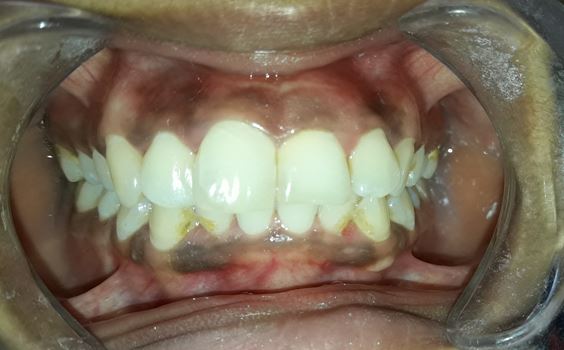

Management of intrinsic discoloration using walking bleach technique in maxillary central incisors

Introduction. Non-vital bleaching is a non-invasive technique to treat the intrinsic discoloration of teeth of several etiologies. Hydrogen peroxide and sodium perborate are commonly used bleaching agents.

Aim. The aim of this case report is to demonstrate the non-vital bleaching technique in maxillary anterior teeth.

Method. Maxillary central incisors were isolated with rubber dam and root canal treatment was performed. Barrier space preparation was done using a heated instrument. Glass ionomer cement was used a barrier material. Mixture of hydrogen peroxide and sodium perborate was placed in the canal and sealed with intermediate restorative material. After 1 week, the procedure was repeated to achieve the desired results.